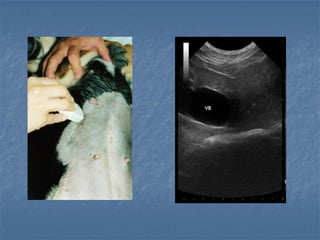

Vesicula biliar atrófica

 Vesícula biliar atrófica

 Alterações inflamatórias